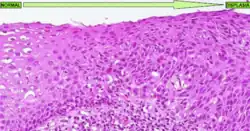

La forma más conocida de displasia es la displasia cervical, bastante común en las lesiones precursoras del cáncer de cuello de útero. Es un tipo de displasia que tiene como causa etiológica el papillomavirus humano y que afecta al cérvix uterino de las mujeres. En este tipo de displasia se observa una diferenciación muy clara del tejido cervical dañado respecto al tejido sano (ver imagen adjunta). En esta enfermedad hay tres grados de displasia diferentes:

- Universidad de Utah, Escuela de Medicina. Imagen de una displasia de cuello uterino; Displasia cervical escamosa de mayor magnificación Descripción en inglés. Último acceso 5 de marzo de 2008.